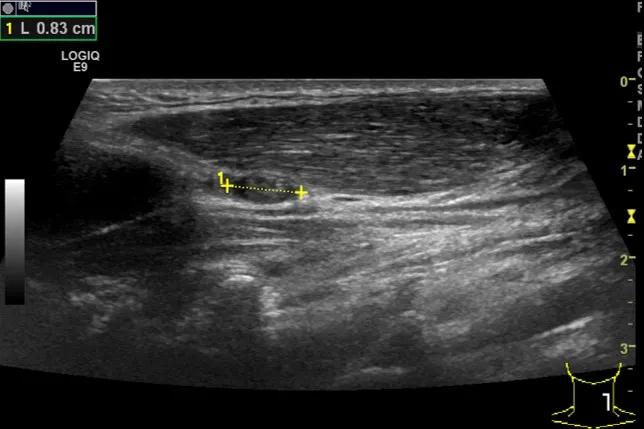

第三例是甲状腺癌患者,双侧甲状腺癌切除术后、碘治疗后一年余效果欠佳,超声显示左颈3区3枚低回声结节,穿刺示甲状腺乳头状癌转移。患者不愿意手术,希望采取局部治疗。对病灶进行液体隔离后采取热消融术,由于淋巴结较小,热消融一分钟左右完全灭活,术后增强影像显示没有脏器充填。

(病例3图例)